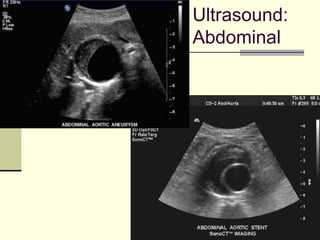

Ultrasound:

Abdominal